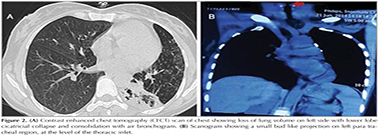

General physical and systemic examination revealed nothing abnormal except fine crepitations in left infra-scapular and infra-axillary region. Laboratory investigations were within normal limits. Pulmonary function test was normal without signs of bronchial obstruction and sputum was negative for acid fast bacilli. Her chest skiagram PA view showed left lower zone infiltrates with air-bronchogram, loss of lung volume on left side and same side shifting of mediastinum, over all finding suggestive of left lower lobe collapse with consolidation (Figure 1). Contrast enhanced chest tomography (CECT) scan of chest showed loss of lung volume on left side with lower lobe cicatricial collapse and consolidation with air-bronchogram while the scanogram revealed a small bud like projection on left para tracheal region, at the level of the thoracic inlet (arrow) (Figure 2A,B). The presence of a narrow stalk connecting the lesion with the posterior wall of the trachea was critical in establishing the diagnosis of a tracheal diverticulum. Furthermore, three-dimensional reconstruction CT ?virtual bronchoscopy confirmed our diagnosis as it showed an orifice of tracheal diverticulum in tracheal wall on left side just below the vocal cord (Figure 3). Fiber optic bronchoscopy (FOB) showed air bubbles and secretions coming out from an opening in the postero-lateral wall of trachea on left side approximate 1 cm below the vocal cords (Figure 4A, B). Further FOB revealed marked narrowing of the left lower lobe bronchus suggestive of cicatricial collapse. The diagnosis of tracheal diverticulum with left lower lobe collapse was made. The barium contrast study performed to look for any esophageal communication, but to fail (Figure 5). Bronchoalveolar lavage taken during FOB, sent for gram stain and pyogenic culture. Patient was referred for surgical management looking at the frequency of symptoms, but she denied for any operative intervention. She was then managed conservatively with antibiotics, mucolytics and vaccinations to reduce the frequency of chest infections and subsequent complication.